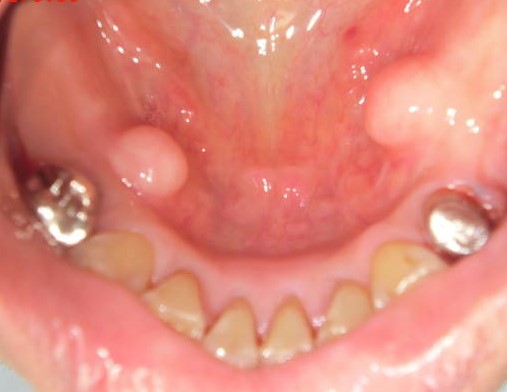

(2)下顎隆起 torus mandibularis

過剰な下顎隆起は義歯の製作、着脱などに大きな支障となります。

その様な場合、下顎隆起形成術が必要となります。

局所麻酔下に20分ほどで終わり、術後の痛みも余りありません。